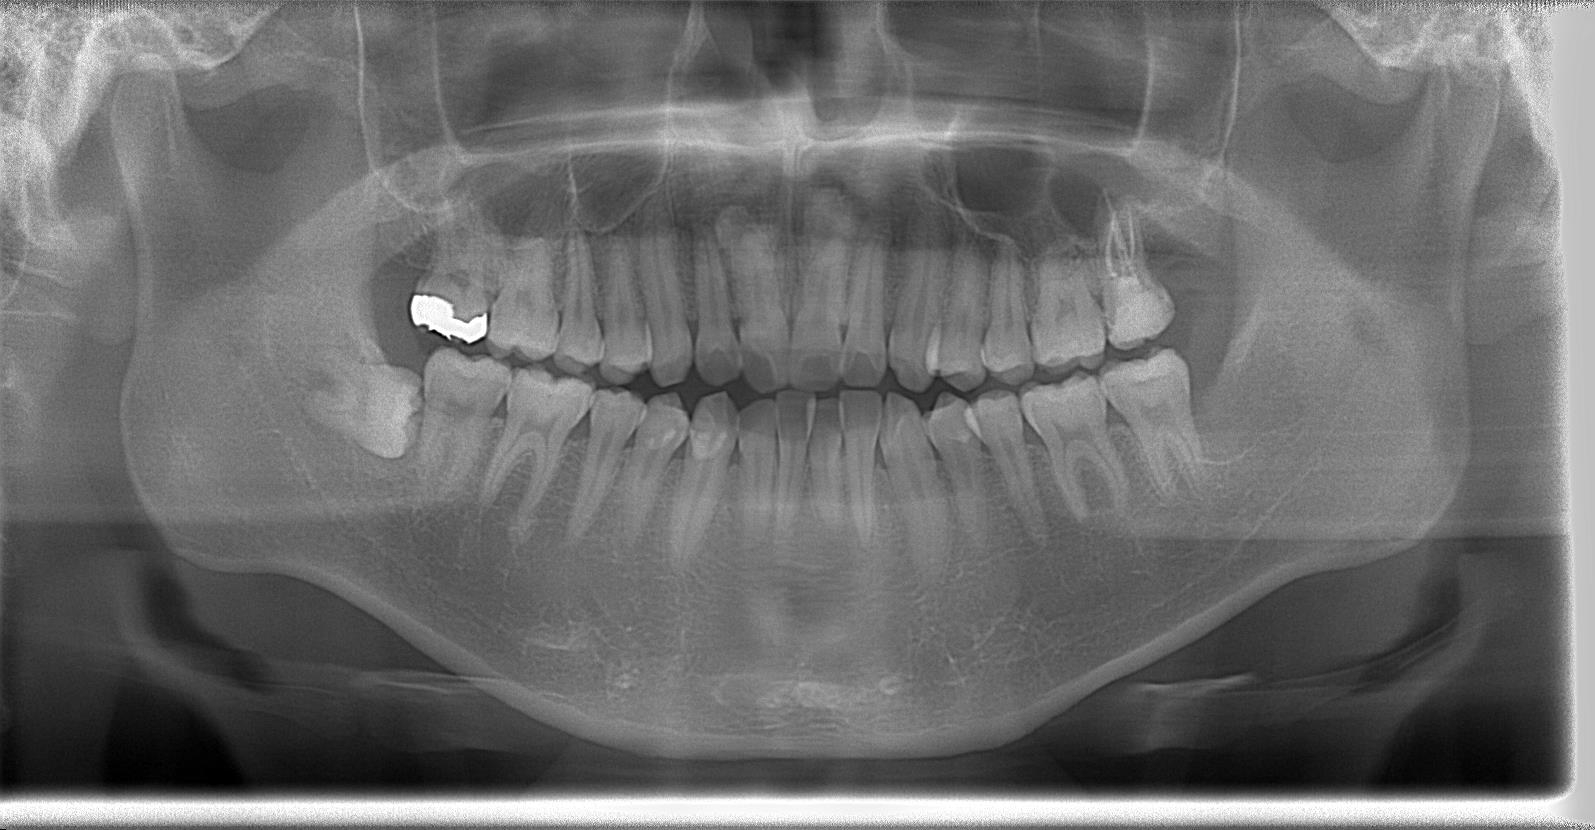

術後パノラマ写真

【After】

術後の痺れなどもなくとても良好です。